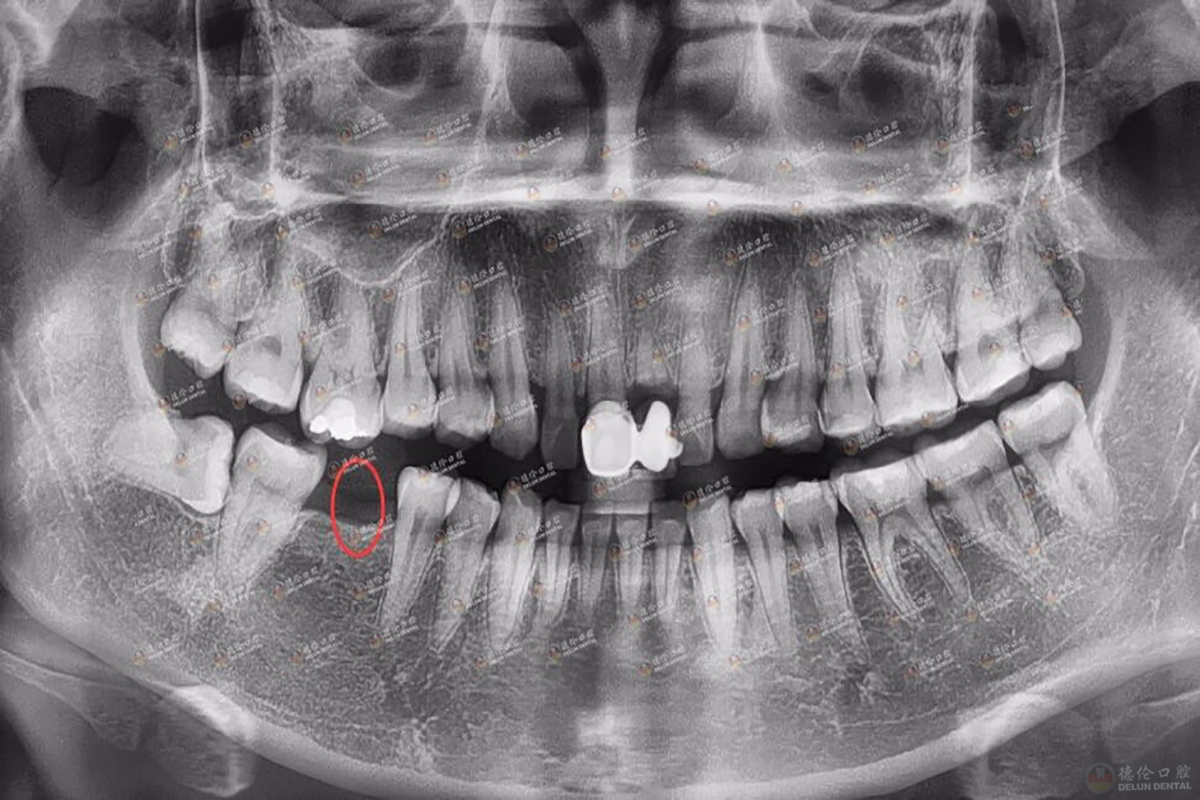

牙x光照片,x光照片

图为邱女士术前x光片

通过x光片,牙医可以了解